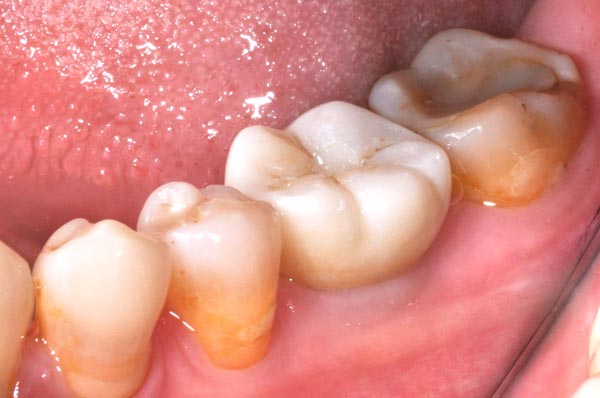

植牙前

植牙全瓷牙冠

植牙後